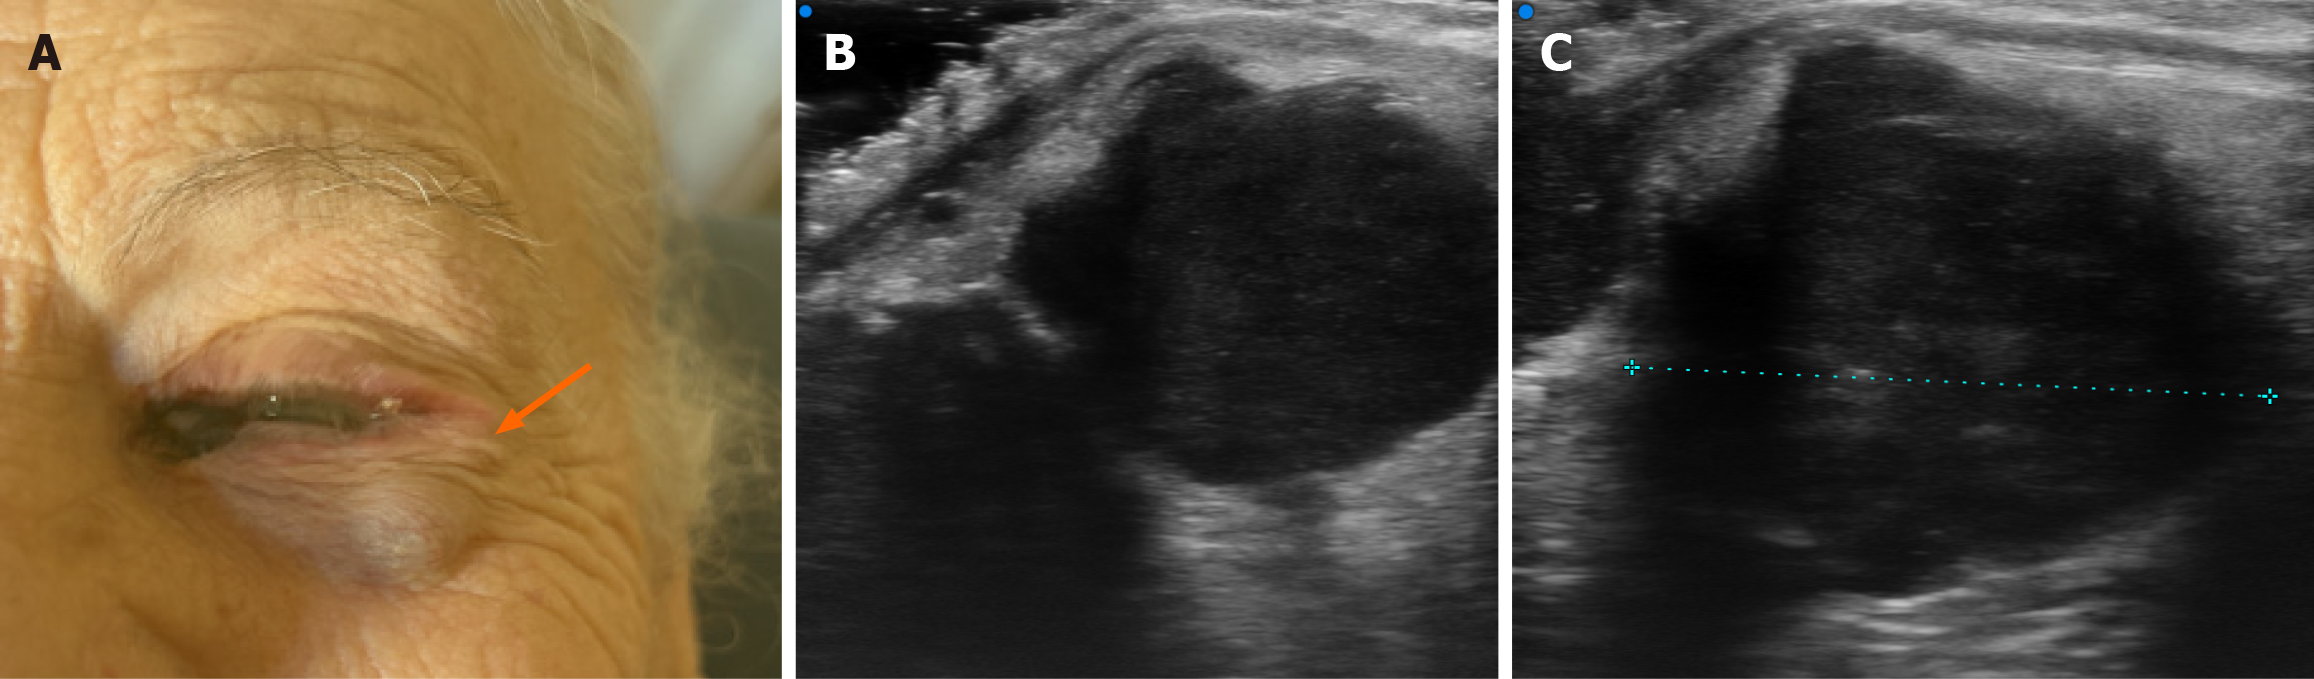

Figure 1 Clinical photograph at the time of referral showing a pigmented lesion at the medial conjunctival canthus and a clearly visible subcutaneous nodule along the lateral orbital rim.

These findings were suggestive of local recurrence of conjunctival melanoma.